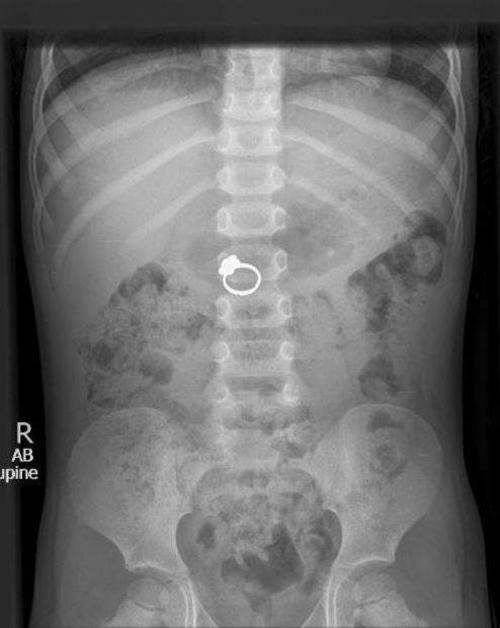

En este sitio se pueden encontrar ejemplos de niños que se tragaron objetos, como un anillo, un par de baterías o incluso un muñeco de Bob Esponja.